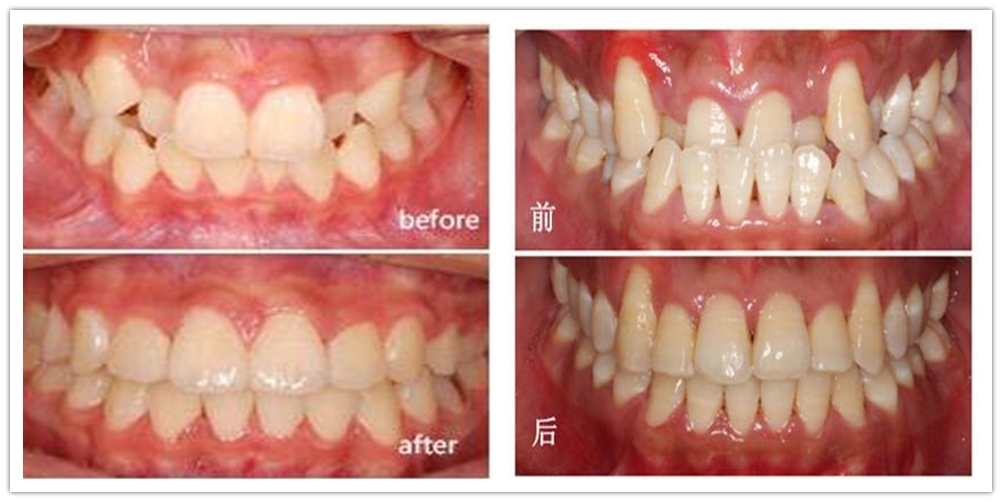

二、口腔正畸:不断提高、完善各种矫治方法(预防矫治、阻断矫治、一般矫治)和矫治器(固定矫治器、活动矫治器、功能性矫治器)的使用。特别是“微种植支抗技术”工作开展以来,极大地缩短了整牙疗程,提高了正畸治疗效果。